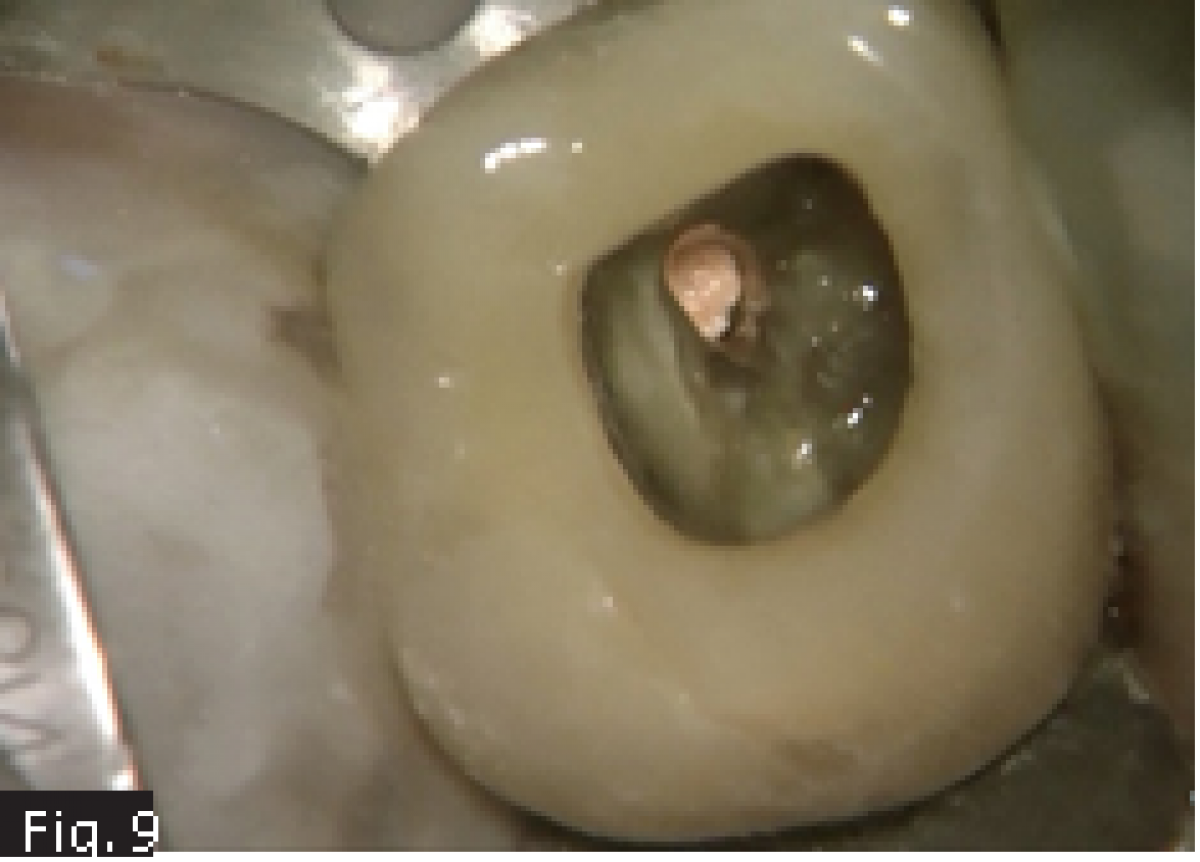

A 62 years old patient was referred to our clinic for endodontic retreatment: the patient reported swelling to the upper left part of the gum. The radiographic examination showed the presence of an existing endodontic therapy and of periapical radiolucencies (Fig. 1). Since the existing therapy could be improved, we decided to retreat the tooth passing through the existing crown. After positioning the rubber dam (Fig. 2), the existing composite filling in the centre of the crown was removed by using a diamond-coated bur driven by a high-speed handpiece. In this way, the access cavity was executed and refined in order to see the pulp chamber(Fig. 3). The existing root canal filling was removed thanks to the use of rotary instruments specifically designed for retreatment, then ultrasonic tips were used to remove the remnants of the pull chamber floor. The chamber was filled with 5 % sodium hypochlorite (Fig. 4) and the MB2 canal, that had not been shaped-cleaned-filled during the initial treatment, was found and it underwent the standard protocol for shaping.

Considering the presence of an endodontic lesion and swelling, a lot of time was dedicated to decontamination of the root canal system (Fig. 5) (18). The device chosen to deliver the irrigating solution right to the working length was IrriFlex (Produits Dentaires SA, Switzerland) (Fig. 6) because, thanks to its flexibility, it was able to deliver the irrigant to the apical third of each root, without any effort, without stopping in case of curvatures. The irrigant was then activated by means of ultrasonic inserts (19) according to the indications given by Tonini et al. (12). After ensuring that the root canals were dry, they were filled according to the warm gutta percha compaction technique (Fig. 8-10). After that, the access cavity was filled by means of a direct composite restoration (Fig. 11) and a post operative x-ray was taken in order to check the final result (Fig. 12).